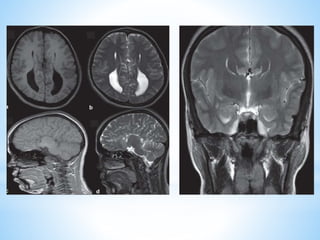

* The hypothalamus constitutes the lateral wall of

the third ventricle.

* Walls of 3rd ventricle merge forming lamina

terminalis anteriorly.

* Lateroposteriorly borders: GP, basal forebrain,

internal capsule, crus cerebri.

* Inferior prolongation of the floor of 3rd ventricle →

pituitary stalk/infundibulum. Which joins the HT